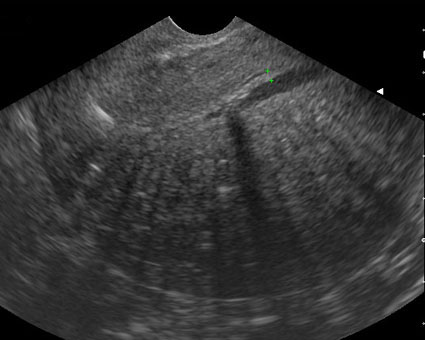

Adénomyose utérine. Asymétrie des parois antérieure et postérieure (Cliché : Dr. C. TALMANT)